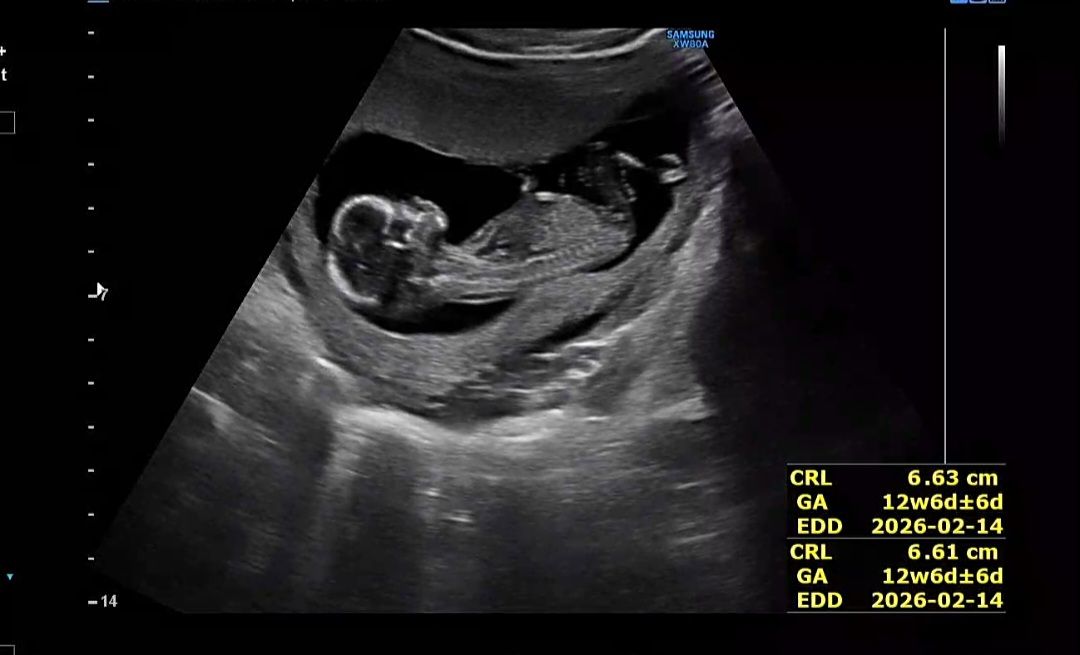

12주 4일 각도법 봐주세요❤️❤️

오늘 12주 4일차 1차 기형아검사하고 왔어요! 목둘레는 다행히 정상 범위~🥹 성별 고수님들.. 한번 봐주실 수 있나용

생식기가 척추선과 평행하면 딸 각도고, 생식기가 위로 올라가 있으면 아들 각도래요ㅎㅎ 요건 장꾸맘님께서 아들 추측해 주신 저희 아기 초음파 사진이에요!